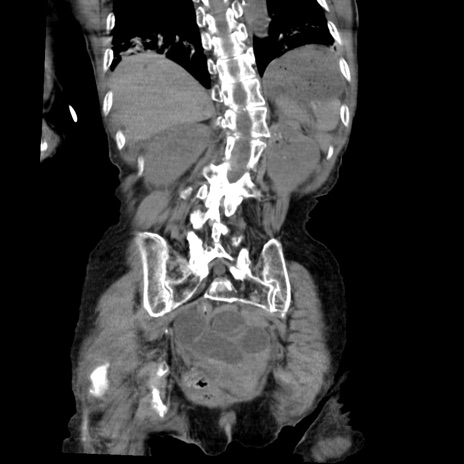

症例27(冠状断像)

【症例】80歳代女性

【主訴】嘔吐、腹痛

【現病歴】数時間前より嘔吐あり。心窩部痛出現し、徐々に右下腹痛あり。その後も数回嘔吐あり救急搬送となる。

【既往歴】左大腿骨頚部骨折手術

【身体所見】腹部は膨隆しているが軟らかく圧痛なし。腸雑音はやや亢進。

【データ】WBC 12000、CRP 19.05